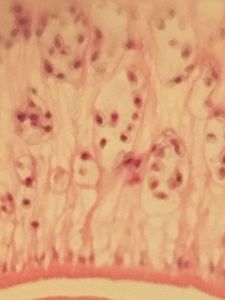

Foldscope number: 0001 493B B5C5 , close-up of detail on a liver fluke, then two brain images; the first showing hemorrhaging (red areas in the amorphous pink tissue [brain]), the second focused on a blood vessel, with dark malaria pigment inside the vessel. This is caused by schizonts – one of the stages of Plasmodium’s asexual replication – lodging in the vessels and causing blockages, leading to the characteristic pathology of cerebral malaria. The dark pigment is a waste product of the parasites, and is derived from haemoglobin.

Foldscope number: 0001 576CAAEF , liver fluke as above, with zoom in on area of liver section with many inflammatory cells.